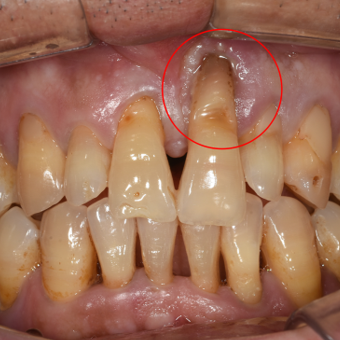

뿌리가 드러난 앞니,

임플란트 + 뼈이식 + 잇몸이식 사례

처음 내원 당시

50대 남성 환자분으로, 뿌리가 거의 드러난 왼쪽 위 앞니는 잇몸뼈도 많이 녹고, 잇몸도 망가진 상태였습니다.

임플란트만 심을 경우 티타늄 뿌리가 보이거나 치아 보철이 지금처럼 길게 보여 비심미적일 것으로 예상되었습니다.